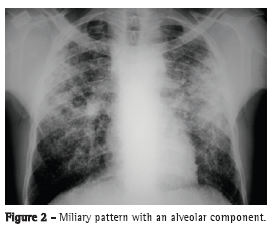

The most common radiological findings are reticular infiltrates and consolidation,(5,6,10,15,17) and cavitation can occur in 27-50% of cases.(6,10,16) Figures 1 to 4 show some of the main radiological patterns in this context.

The leading cause of ICU admission was respiratory failure, and Acute Physiology and Chronic Health Evaluation II (APACHE II) scores ranged from 13 to 23 in most of the studies.(5,6,10,15,17) Some authors evaluated the factors associated with the development of respiratory failure and the need for MV. Gram-negative pneumonia or sepsis, COPD, history of poor compliance with tuberculosis treatment, and cancer were predictors of respiratory failure.(9) In a series of 13 cases, 7 and 6 patients, respectively, had miliary/disseminated tuberculosis and tuberculous pneumonia requiring intensive care. Patients with miliary/disseminated tuberculosis were more likely to require MV than were those with tuberculous pneumonia (18.9% vs. 0.8%; p < 0.0001).(8)

The time from onset of symptoms to initiation of antituberculosis treatment has been reported to be over 30 days in 28.8-34.0% of cases.(6,17) The time from admission to initiation of appropriate treatment was evaluated in only one study, which reported a mean of 4.3 days. In that retrospective study, the time from admission to initiation of treatment was shorter in patients with miliary tuberculosis than in those with tuberculous pneumonia (2.8 ± 2.5 days vs. 5.0 ± 7.0 days; p = 0.048).(16) There can be a delay in diagnosis and, consequently, in initiation of treatment because it is difficult to differentiate tuberculous pneumonia from severe bacterial pneumonia on X-rays. Considering this difficulty in distinguishing the two pathologies, one study evaluated the differences between ICU patients with severe pneumonia and tuberculosis and those with severe pneumonia without tuberculosis in terms of their clinical and radiological characteristics. Symptom duration longer than two weeks and the presence of micronodules or a cavitary pattern on chest X-ray were significantly associated with active pulmonary tuberculosis.(20) In addition, a miliary pattern on chest X-ray can also be misinterpreted as congestive heart failure.(18)